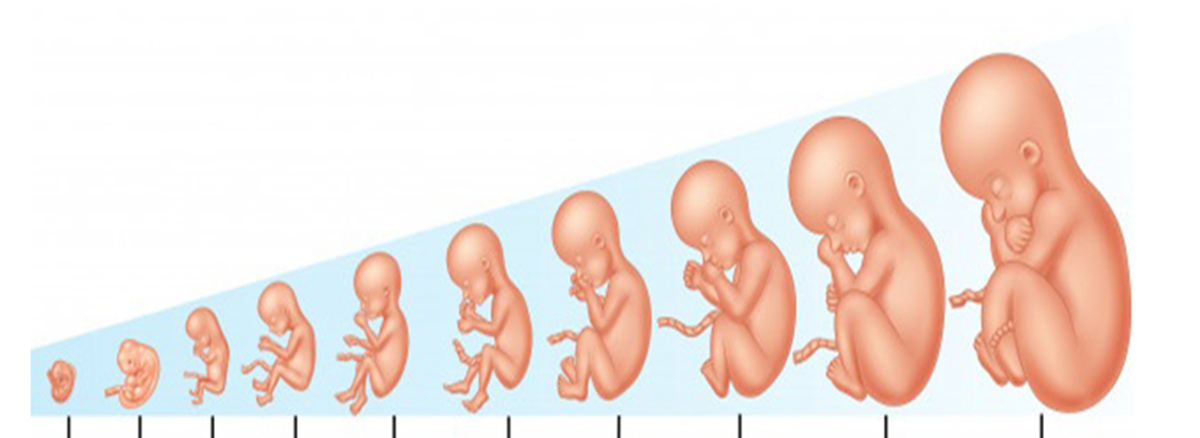

* سه ماهه اول بارداری (هفته 1 تا 13)

سه ماهه اول بهعنوان حساس ترین دورهی بارداری شناخته می شود. در این بازه، اغلب تغییرات بنیادین در بدن مادر و جنین اتفاق می افتد. بسیاری از سقطها نیز در این دوره رخ میدهد، به همین دلیل مراقبت ویژه پزشکی اهمیت بالایی دارد.

🔸 هفته 9 تا 13: پایان تثبیت و رشد سریع

جنین وارد مرحله جنینی میشود و شکل انسانی پیدا می کند.

چشمها، گوشها، بینی، انگشتان دست و پا رشد می کنند.

استخوانها شروع به شکل گیری می کنند و جنین قادر به حرکتهای کوچک است.

* سه ماهه دوم بارداری (هفته 14 تا 27)

سه ماهه دوم بهعنوان دوران طلایی بارداری شناخته می شود، زیرا بسیاری از علائم اولیه مانند تهوع و خستگی کاهش می یابد و مادر احساس آرامش و انرژی بیشتری می کند.

🔸 هفته 14 تا 17: تثبیت وضعیت و شروع حرکت جنین

رشد جنین با سرعت بالا ادامه دارد. استخوانها سفت تر و ماهیچهها در جنین قوی تر می شوند.

🔸 هفته 22 تا 27: رشد تکاملی و آمادگی برای بقا

پوست جنین چروکیده اما پوشیده از ماده ای به نام ورنیکس میشود.

ریهها شروع به بلوغ می کنند، اگرچه هنوز کامل نشده اند.

سه ماهه سوم (هفته 28 تا 40)

هفته 28 تا 35

وزن جنین بیشتر می شود و اندام های او تقریبا به تکامل رسیده اند. جنین می تواند صداها را بشنود و حتی عکس العمل نشان دهد. مادر احساس سنگینی بیشتر و خستگی بیشتری دارد.

هفته 36 تا 40

جنین برای تولد آماده می شود و سر او به سمت لگن پایین می آید. انقباضات رحمی می تواند آغاز شود و مادر وارد فاز آمادگی برای زایمان می شود.